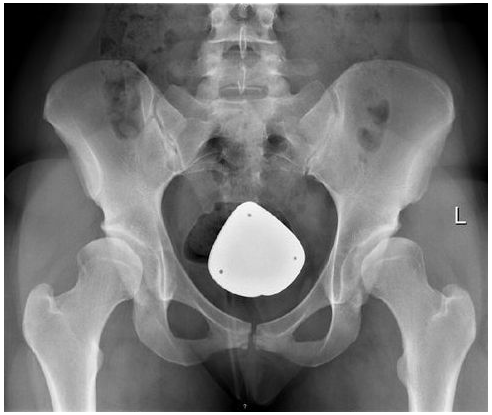

The hip joint is formed with a ball and socket. The upper region of the femur bone which comprises the hip ball joint meets a socket of the pelvic bone. The ball is ideally supposed to move in different directions, but stay connected inside this pelvic socket. This helps humans move their hips in various directions comfortably. These also fold the body weight so that we can walk and run freely. When there is developmental dysplasia of the hip or DDH, the joint formation is less than ideal, which will cause a problem in the movement of a child if left untreated.